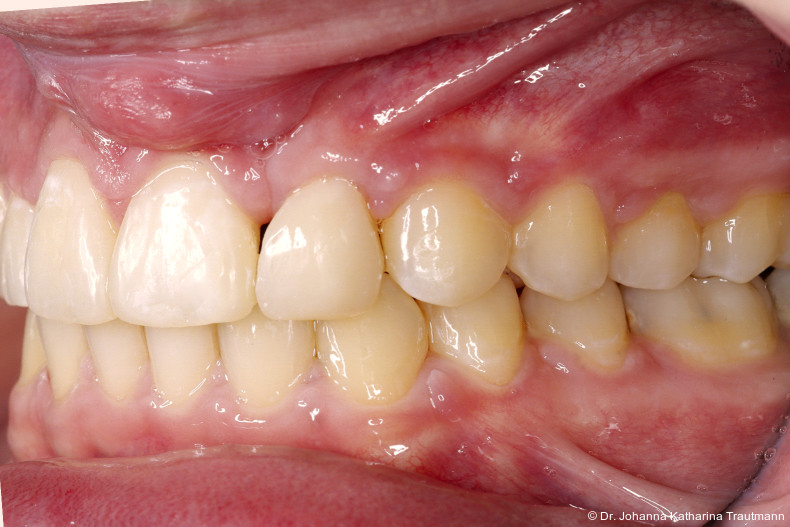

Das Fernröntgenseitenbild zeigte eine skelettale Klasse IIAnomalie mit einem Wits von 5,6 mm, bei einer tiefen Konfiguration (ML NL = 16,5°) mit bialveolär retrudierten Fronten (OK1NA = 5,9°; UK1NB = 10,4°), was sich auch in der Modellanalyse widerspiegelte. Hier zeigte sich zudem ein schmaler Oberkiefer mit multiplen Kippungen und Rotationen in der Front, einem hypoplastischem 22 sowie einer Mesialwanderung des 16. Des Weiteren zeigte sich eine asymmetrische Bisslage mit 1 PB distal rechts und ½ PB distal links bei einem Overjet von 2,5 mm sowie einem Overbite von 5 mm. Während im Unterkiefer bereits die zweite Zahnwechsel phase begonnen hatte, zeigte sich im Oberkiefer noch kein Wechsel in den Stützzonen. Gerade bei Patienten mit Spaltbildungen ist eine engmaschige Überwachung des Durchbruchs der oberen Eckzähne essenziell. Während bei der Allgemeinbevölkerung die Prävalenz von verlagerten Eckzähnen bei ca. 2,8 Prozent liegt2, ist diese bei Patienten mit Lippen-Kiefer-Gaumen-Spalten um den Faktor 10 erhöht.3, 4 Als klassische Risikofaktoren gelten zudem Platzmangel, transversale Enge aber auch Fehlstellungen, Nichtanlagen oder Hypoplasien der zweiten Schneidezähne. Diese übernehmen normalerweise die Funktion der Leitschiene für den S-förmigen Durchbruch der Eckzähne. Im vorliegenden Patientenfall kommen also mehrere Risikofaktoren für eine Verlagerung zusammen, was die rechtzeitige Diagnostik zur Abklärung einer Durchbruchsproblematik rechtfertigt. Da im Spaltbereich auch zusätzlich ein ausgeprägtes Knochendefizit vorliegen könnte, sollte auch immer die Option einer sekundären Osteoplastik abgewogen werden, deren Indikation und Timing optimal zum Durchbruch der Canini angepasst werden sollte.5